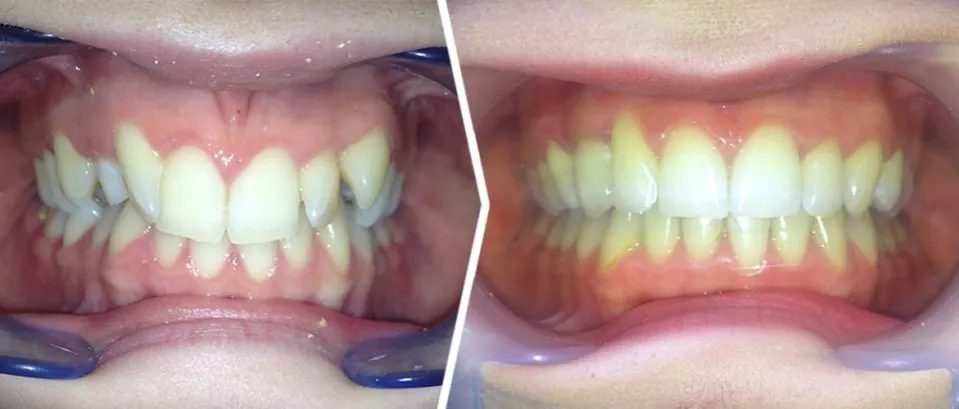

Co może zrobić dentysta? Przegląd zabiegów od higienizacji po odbudowę protetyczną

Zakres możliwych zabiegów stomatologicznych, które dentysta może zaproponować, jest szeroki i zależy od stanu Twojego uzębienia. W zależności od stopnia zniszczeń, leczenie może obejmować:

- Profesjonalna higienizacja: Podstawowy zabieg, który obejmuje skaling (usuwanie kamienia nazębnego) i piaskowanie (usuwanie osadu i przebarwień). Jest to pierwszy krok do oczyszczenia jamy ustnej.

- Leczenie wszystkich ubytków próchnicowych: Wypełnianie ubytków materiałami kompozytowymi lub innymi, w zależności od lokalizacji i wielkości próchnicy.

- Fluoryzacja: Zabiegi remineralizacji szkliwa przy użyciu preparatów z fluorem, które pomagają wzmocnić osłabione zęby.

- Leczenie kanałowe: W przypadku głębokiego zniszczenia zęba, gdy próchnica dotrze do miazgi, konieczne może być leczenie kanałowe, aby uratować ząb przed ekstrakcją.

- Odbudowa zębów za pomocą koron protetycznych: Gdy zęby są mocno osłabione, połamane lub mają duże ubytki, odbudowa za pomocą koron protetycznych (np. ceramicznych) jest często jedynym sposobem na przywrócenie im funkcji i estetyki.

- Ekstrakcje i leczenie protetyczne: W najgorszych przypadkach, gdy zęby są nieodwracalnie zniszczone, konieczne może być ich usunięcie. Następnie można zastosować leczenie protetyczne, takie jak mosty, protezy ruchome lub implanty stomatologiczne, aby uzupełnić braki w uzębieniu.